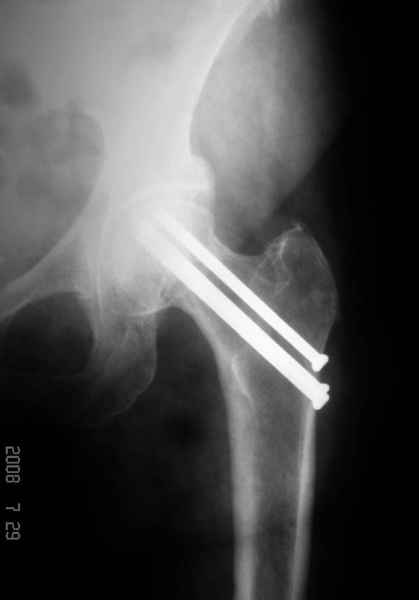

77 летняя больная направлена в нашу клинику на дальнейшее лечение. Из истории, травму получила в сентябре 2007 года и по поводу перелома шейки бедра больная была проперирована тремя каннюлированными шурупами с явным нарушением технологии установки шурупов. Внизу вместо одного шурупа имеется два, что привело к стрессу латерального кортекса. Через месяц по поводу ятрогенного подвертельного перелома сделана фиксация длинной Гамма 3. Установлен без проксимальной блокировки? (set screw). В данный момент имеется несостоятельность конструкции и ложный сустав. Передвигается с помошью костылей, конечность укорочена на 2 см. Какие будут рекомендации?Djoldas Kuldjanov, MDDepartment of Orthopedic SurgerySt. Louis University Medical Center

Я не вижу на снимках нестабильности конструкции (разве что гнутый дистальный винт).

Михаил, здравствуйте. Если присмотреться - на четвертом снимке есть перелом гвоздя по отверстию.

Видимо, проблем тут две: во-1-х, центральный отломок был оставлен в варусно-сгибательной установке, во-2-х, не динамизировали вовремя.

Нижние винты хотели сломаться, но, увы, один не сломался, и тогда сломался гвоздь. Хотя и при динамизации в таком положении отломков

могло не срастись.